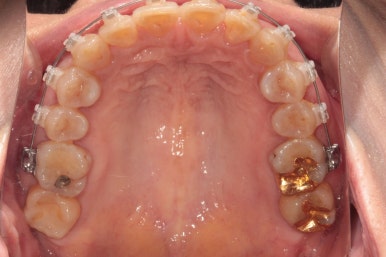

클리피씨 교정을 합니다.

TOMY 사의 클리피씨는 가장 많이 쓰이는 교정장치입니다.

위에 보이는 사진은 교정장치를 붙이고 불과 4개월 후 입니다!

생각보다 위턱 앞니가 빨리 가지런해 진 것을 확인할 수 있습니다.

아래 앞니만 조금 더 가지런해지면... 될 것 같은 느낌이네요.

그리고 교합면 사진을 통해 전체적인 진행 상태도 파악할 수 있죠.

씹는면에서 보아도 상당히 가지런히 완성된 것을 보실 수 있습니다.